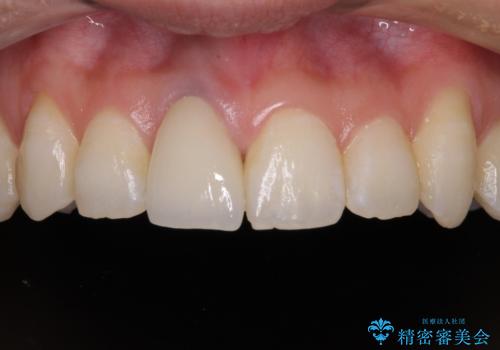

被せものと土台の歯との境目が、歯茎の下に隠れるように調整し、段差もないため、審美性・清掃性のどちらの観点からも理想的な被せものになり、患者様は満足されました。